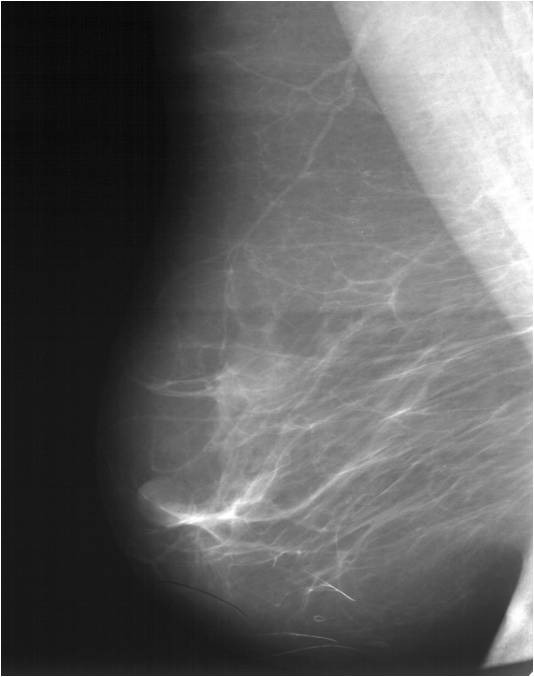

Для выявления злокачественных опухолей молочной железы существует определенный алгоритм диагностики, и его первичный элемент — маммографический скрининг. Чувствительность этого метода диагностики для опухолей от 2 мм до 5 мм составляет около 85%. Маммографическое исследование выполняют в двух проекциях.

Цифровая маммография РМЖ